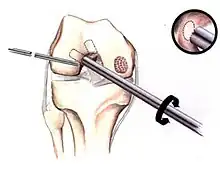

Intact lesions

If non-surgical measures are unsuccessful, drilling may be considered to stimulate healing of the subchondral bone. Arthroscopic drilling may be performed by using an antegrade (from the front) approach from the joint space through the articular cartilage, or by using a retrograde (from behind) approach through the bone outside of the joint to avoid penetration of the articular cartilage. This has proven successful with positive results at one-year follow-up with antegrade drilling in nine out of eleven teenagers with the juvenile form of OCD,[53] and in 18 of 20 skeletally immature people (follow-up of five years) who had failed prior conservative programs.[54]